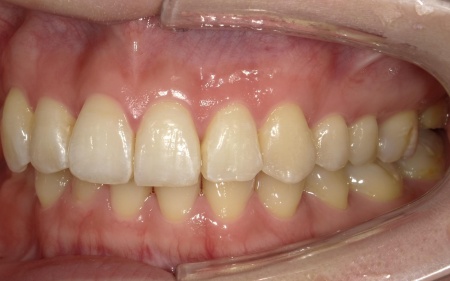

20代女性 前歯の歯並びをマウスピース矯正装置インビザラインGoで改善した症例

治療開始から約3ヶ月後、14枚目のアライナーの装着期間が終了したタイミングで歯並びの状態を確認しました。

確認したところ問題なく歯が動いていたため、歯に装着していたアタッチメントを取り外しています。

画像をクリックすると拡大・詳細コメントを確認いただけます